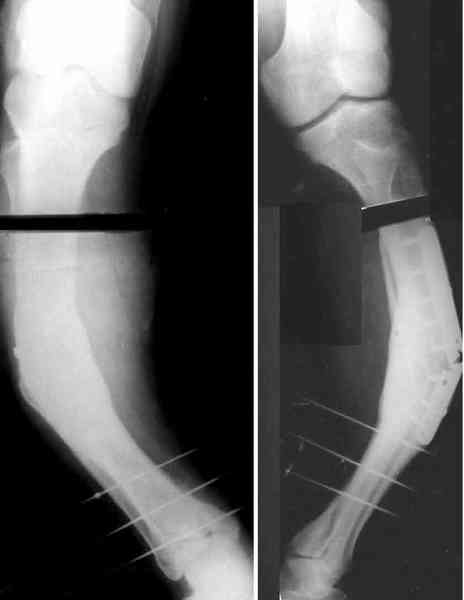

Для продолжения темы - несколько картинок.

Пациент 30 лет, лет пять назад оперирован по поводу перелома голени пластиной. Находясь на героине, нарушил режим, пошел, сломал и ногу и

пластину, но перелом сросся.

В приложении - внешний вид и рентген.

Мнения?

Лукавить не буду, я его уже вылечил. Но применил немного необычную тактику по отношению к пластине - результат после обсуждения...

Там не винты (может, плохо видно), а сломанная пластина, вросшая в кость.

Пластинку и винты мне удалось разглядеть только на профильной проекции, точнее, трехчетвертной, судя по виду коленного сустава (правый снимок). На фасной - вообще не могу разобрать, где она :( Но, в конце концов, можно и не видя ее сказать, что уровень остеотомии может быть и другим, ниже или выше пластинки, придется только компенсировать смещение по ширине, которое появится при полном устранении угла не на вершине.